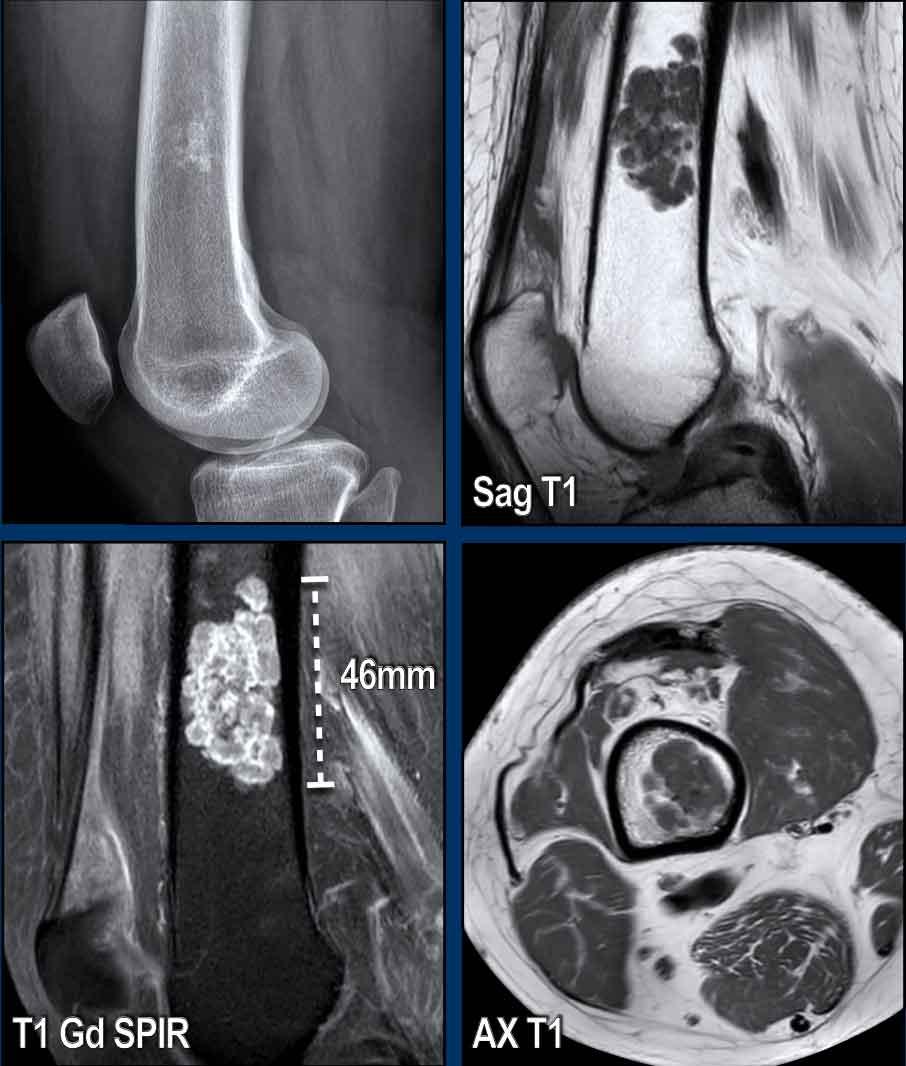

Hình ảnh

Hình ảnh X-quang cho thấy một vùng nhỏ vôi hóa dạng bỏng ngô ở thân xương đầu xa.

Hình ảnh MR cho thấy tổn thương 4,6 cm ở thân xương đùi đầu xa với sự lan rộng đến vỏ xương (lấp đầy từ thành này đến thành kia).

Lưu ý rằng tổn thương có vẻ nhỏ hơn trên phim X-quang do vôi hóa hạn chế.

Các vôi hóa và ngấm thuốc dạng vách-nốt xác nhận bản chất sụn của khối u.

Không có hình ảnh xói mòn vỏ xương trên hình ảnh T1W trục ngang.

Kết luận

Tổn thương khá lớn để chẩn đoán u sụn nội xương.

Như đã đề cập trước đó, chúng tôi sử dụng ngưỡng giới hạn là 5 cm. Có sự lấp đầy toàn bộ, nhưng không có dấu hiệu xói mòn vỏ xương. Không có các đặc điểm xâm lấn (như phản ứng màng xương, phù tủy xương).

Được chẩn đoán là ACT và theo dõi

bằng phương pháp chờ và quan sát.

Sau 5 năm theo dõi, đường kính theo chiều đầu-đuôi tăng 6 mm.

Không có các đặc điểm đáng lo ngại khác và bệnh nhân tiếp tục được theo dõi.

Trường hợp này đã được trình bày trước đây.

Nhìn lại hình ảnh MRI trước đó được thực hiện 5 năm trước, tổn thương đã tăng trưởng 6 mm theo chiều sọ-đuôi.

Cũng lưu ý sự mở rộng của tổn thương về phía trước (mũi tên vàng).

Không có hiện tượng mỏng vỏ xương, phù tủy xương hay viêm màng xương.

This lesion is an

ACT and remains in follow-up.